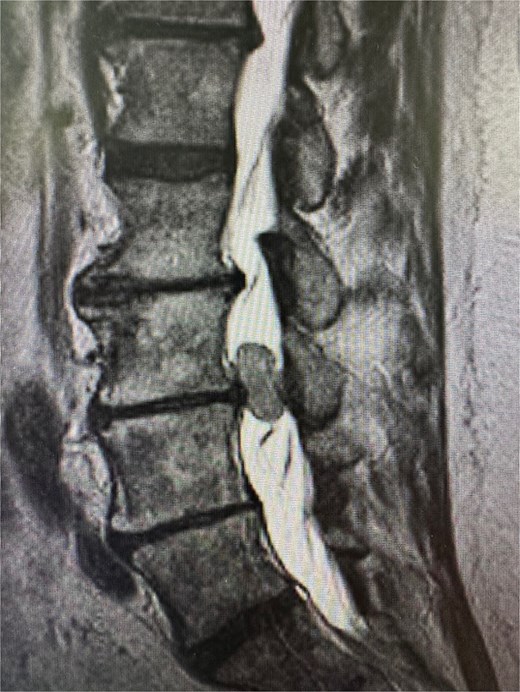

Physical examination was unremarkable, except for tenderness at the right sacroiliac joint. Neurological testing revealed normal reflexes and strength. Sagittal T2-weighted MRI of the lumbar spine demonstrating a well-circumscribed intradural extramedullary mass measuring 0.9 × 1.4 × 1.9 cm at the L3–L4 level. The lesion exhibited intermediate signal intensity (Fig. 1). Other differential diagnoses at this time included meningioma, cystic lesions, infectious processes, or metastases. The patient was referred to neurosurgery.

Sagittal T2-weighted MRI of the lumbar spine demonstrating a well-circumscribed intradural extramedullary mass measuring 0.9 × 1.4 × 1.9 cm at the L3–L4 level. The lesion exhibits intermediate signal intensity.